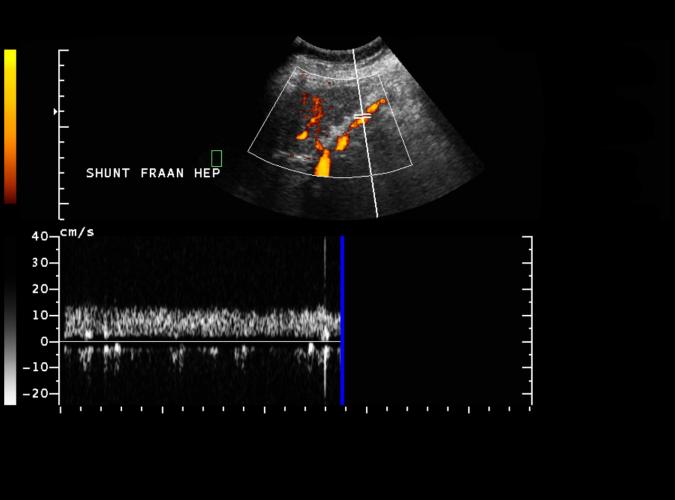

Long. vänster leverlob.

Spektral-Doppler visar blodflöde riktat från levern, som vid portal hypertension i patienten 3a,b,c med biliär cirrhos.